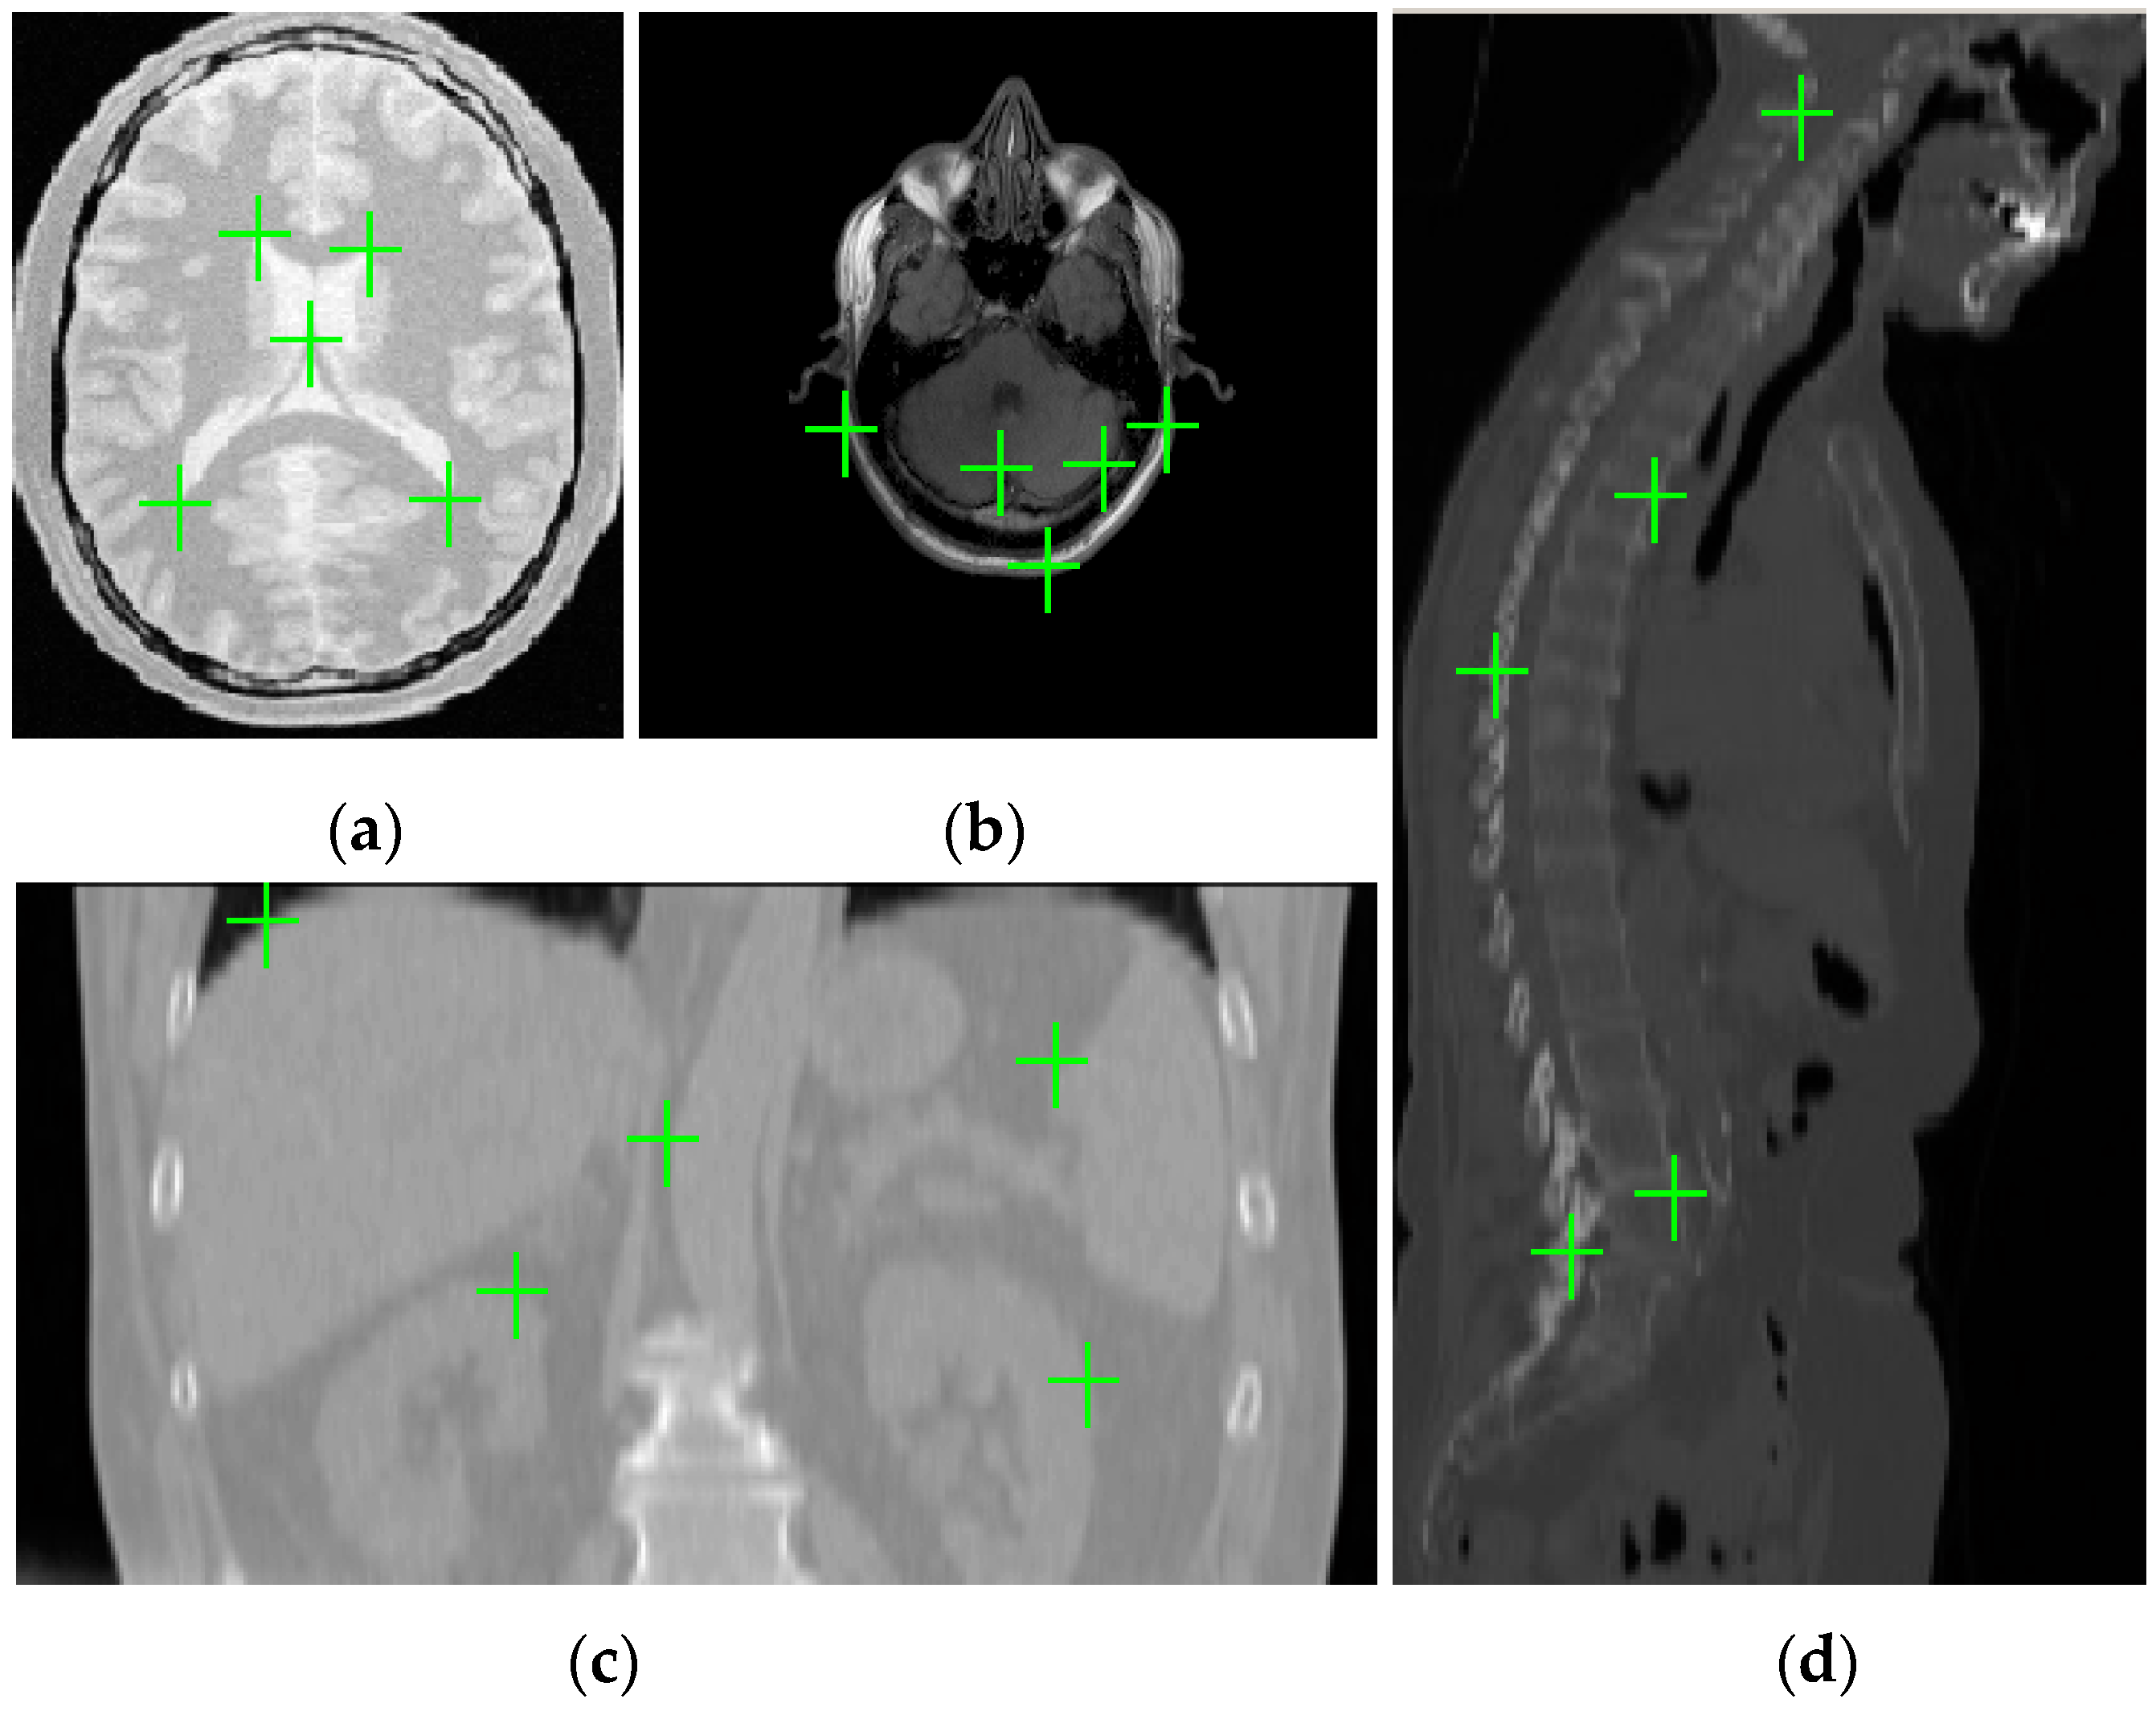

where is the synthetic deformation (i.e., the ground truth generated by using a linear combination of radial basis functions), is the deformation that is estimated by the registration methods, and N denotes the number of landmarks selected manually based on doctors’ advice from the reference images. For each pair of reference and float images, different synthetic deformations will be applied to the float image for 25 times and we will manually select 90 (N = 90) landmarks from each 3D reference image to compute the TRE. The mean of TREs values for registering 25 deformed images will be used to appreciate the registration accuracy. Figure 4 gives an example of chosen landmarks in one slice of simulated 3D PD weighted image and real 3D T1 weighted image for MR image registration, 3D CT image for CT-MR image registration and 3D CT image for CT-PET image registration.

Figure 4.

Landmarks in one slice of three-dimensional (3D) medical images. (a) simulated proton density (PD) weighted image; (b) real T1 weighted image; (c) abdomen computed tomography (CT) image; and, (d) whole-body CT image.